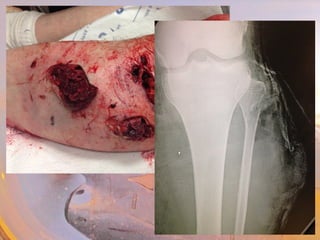

Crush Injury

occurs when body part subjected to high degree of force

or pressure

Blunt Force Trauma

Bleeding

Bruising

Fracture

Laceration

Compartment Syndrome